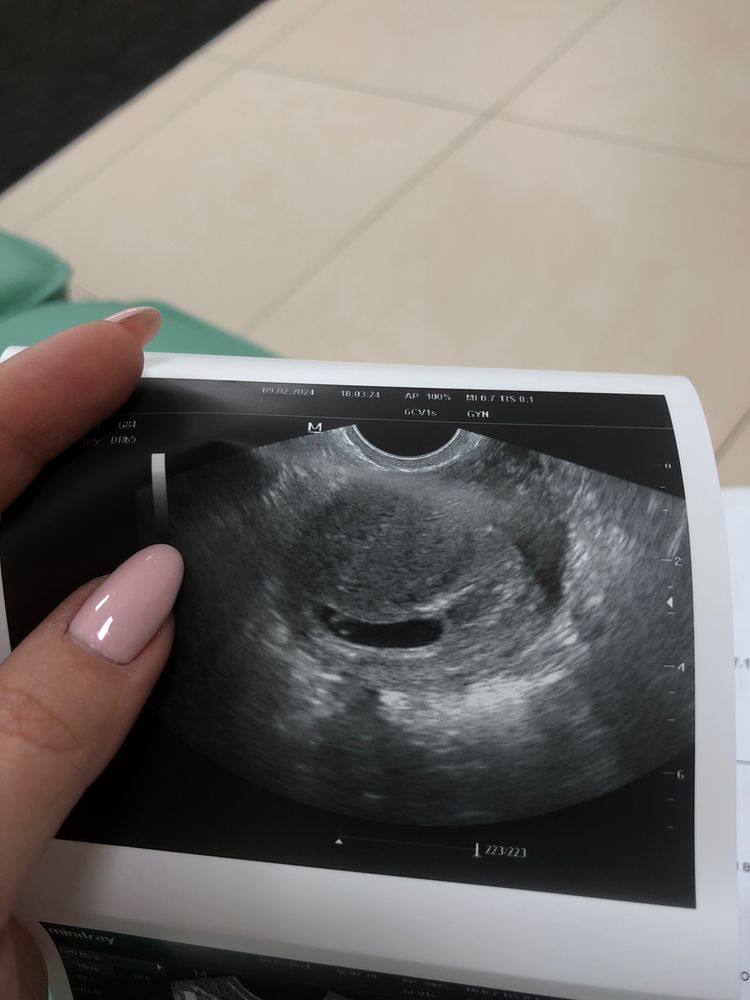

Сегодня ровно 6 акушерских недель, на узи сб не было..( гинеколог сказала, что все идет хорошо, что беременность развивается. Но я так много слышала, что сб слушают уже на пятой неделе, а у меня шестая… Плодное яйцо прикрепилось ко дну матки, гинеколог говорит что именно из-за этого пульсация пока только зрительно видна, но не слышно.

p.s. Показала узи своей подруге, она в прошлом акушер-гинеколог, она сказала, что если бы я была ее пациенткой, она бы меня зря не обнадеживала и отправила на мед.аборт, так как эмбрион не визуализируется, из чего она делает вывод что это анаэмбриония. Меня это так подкосило, что весь вечер я просто билась в истерике. Морально готовлюсь к худшему.